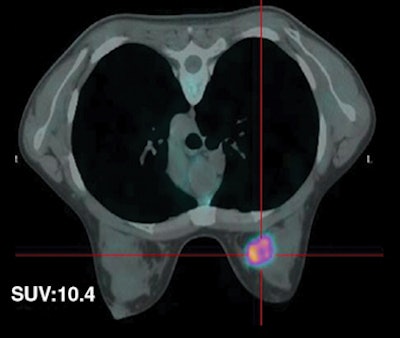

| Fifty-five-year-old woman with ductal infiltrating adenocarcinoma measuring 15 mm in maximum transverse diameter. Axial fused PET/CT images obtained with patient in prone position at time point 1 (above) and time point 2 (below) show corresponding standard uptake values. All images courtesy of the American Roentgen Ray Society. |

![]() |